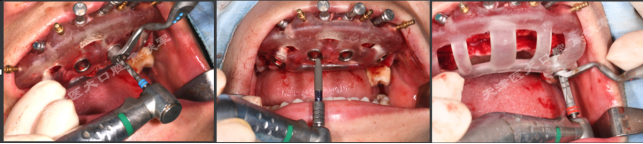

上颌即刻种植即刻修复手术过程

· 上颌360数字化序列导板+预成临时修复体

· 拔除部分牙齿,翻瓣,利用剩余牙齿支持组合导板,辅助基部导板就位固定,基部导板上缘做为去骨线,精确去骨。

· 拔除部分牙齿,翻瓣,利用剩余牙齿支持组合导板,辅助基部导板就位固定,基部导板上缘做为去骨线,精确去骨。

· 全程导板就位,引导种植体植入,安装复合基台。

· 种植体植入位置偏腭侧,唇侧骨量过于丰满,上颌骨前突,去骨修整骨边缘。

· 口内pick-up 固定临时修复体,患者上下颌咬合关系良好。

· 术后CBCT检查可见种植体植入位置佳,与术前设计一致。